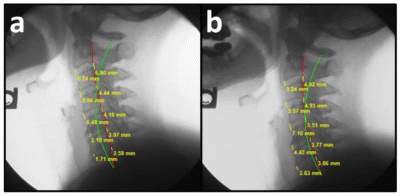

- Disc Height Restoration: The study documented a statistically significant increase in both anterior and posterior cervical disc heights (C2–C7) following the restoration of the cervical lordosis.

Validated Outcomes: Using the Harrison Posterior Tangent Method to measure cervical curve and a reliable and valid measurement of disc height, the study confirms that restoring the spine’s sagittal alignment facilitates a better environment for disc health and nutrient exchange.